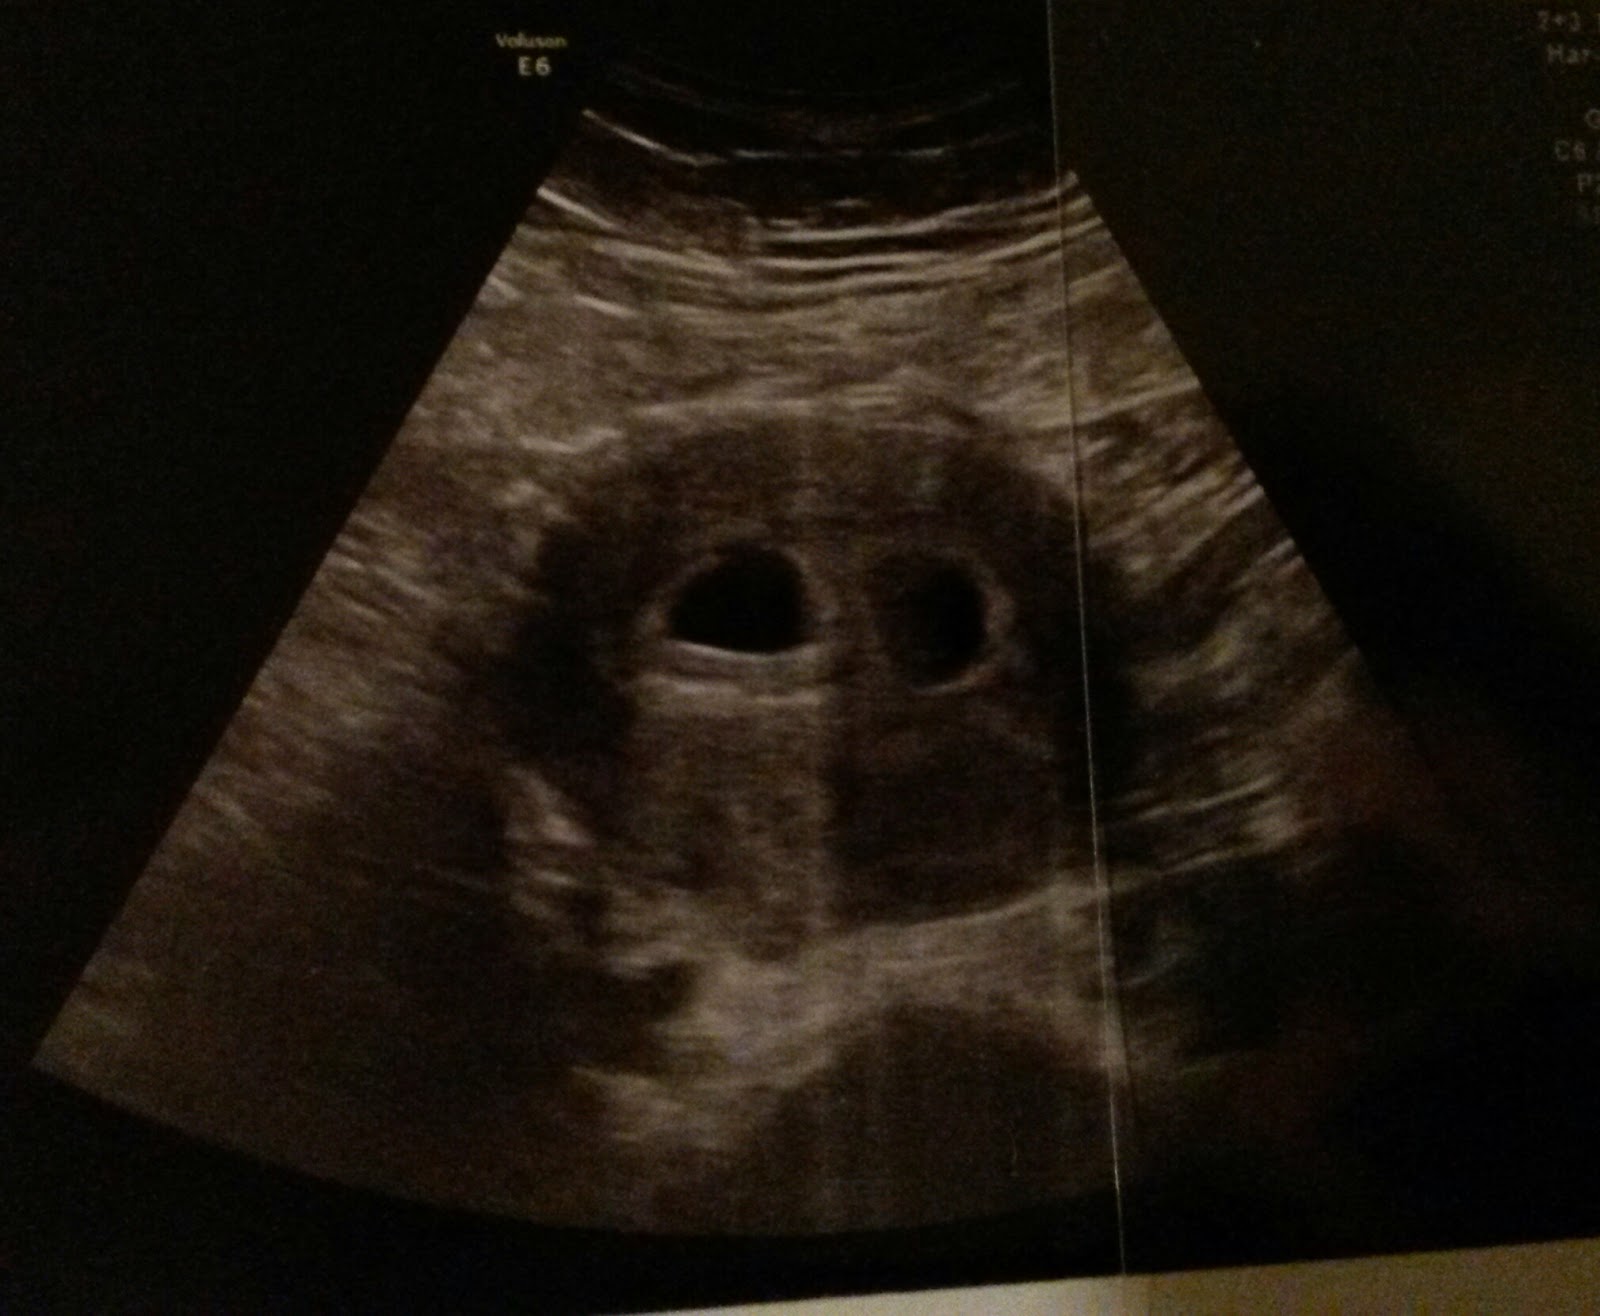

FA: "Nein, Sie haben auch Zwillinge. Da: eins, zwei."

![]() |

| Hasentotenkopfpiraten? |